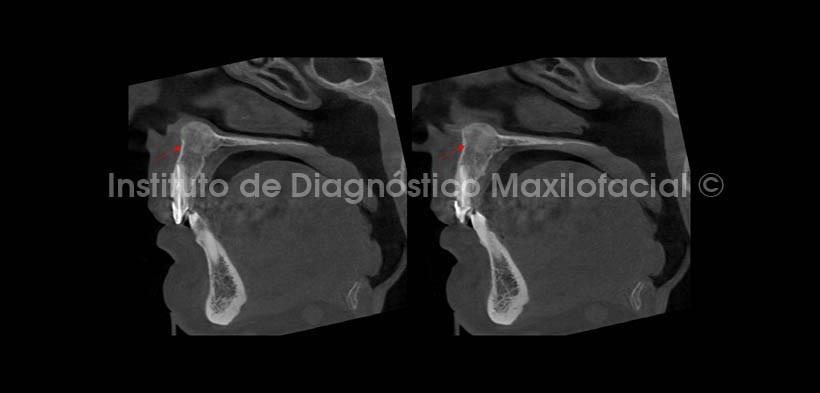

Se realizaron cortes multiplanares; en los cuales se observa el leve estrechamiento del conducto nasopalatino en su porción más superior en el corte coronal (Fig. 3), además del mencionado desplazamiento cefálico del piso de fosa nasal del lado derecho. En cortes axiales (Fig. 4), se aprecia el ocupamiento de la parte anterior de la fosa nasal derecha condicionado por el crecimiento de la lesión, observando la cercanía de esta con la espina nasal anterior, y en cortes sagitales (Fig. 5) se evidencia un leve desplazamiento de la tabla ósea vestibular.